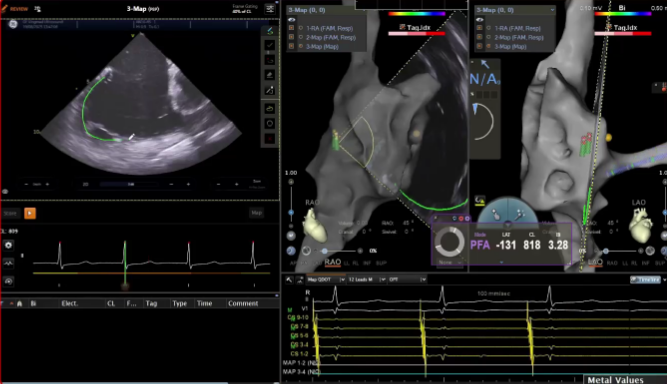

在本次电生理手术直播周期间,20位资深术者通过实时手术演示,全方位展现了 VARIPULSE脉冲消融系统在房颤治疗中的高效与绿色优势,将其临床性能推向极致。手术数据亮眼——全场直播的平均消融时间仅28分钟,充分印证了该系统的高效性;学术交流同样热烈,超50位领域专家齐聚线上,围绕‘麻醉方案优化’‘、“术式创新选择”、”并发症预防策略”等脉冲电场消融领域的核心热点话题,展开深度研讨与观点碰撞。

无论是0射线还是低射线下,PFA总体安全性非常高了,阵发性房颤血管痉挛几乎没有发生,溶血只要控制次数概率非常低。PFA时代主要并发症与房穿相关,通过ICE(心腔内超声)+T3D技术实现精准房间隔穿刺,可保证手术安全;PFA治疗安全性较高,损伤主要与贴靠情况相关,我们需要保证足够的贴靠度和压力值,才能有足够的损伤,可调弯鞘管对导管到位帮助很大,让尽可能多的电极产生很好的贴靠再放电,可避免无效放电。

很多时候我们都采用零射线,ICE指导下建的模型,和三维CT相媲美,且可以标记肺静脉口部,指导PFA消融过程。PFA使得消融效率大幅提升,但手术过程中充分抗凝很重要!术中有时会出现ACT(活化凝血时间)不达标,或手术结束时 ACT仍未达到350s的情况;目前肝素给药剂量为100IU/kg,有国外专家建议可以200IU/kg加肝素,尽快使ACT达标。术后ACT还高的话,可用鱼精蛋白对冲。

在PFA房颤手术中,三维很重要,可以帮助判断贴靠怎么样,寻找哪里有gap,同时现在是绿色电生理时代,只有三维才能做到绿色。PFA房颤手术中穿刺需要偏前偏低,结合ICE的穿刺能够使可调弯鞘管配合PFA导管在右下肺贴靠更好。术中肝素补足很重要,ACT300以上能大大减少无症状脑损伤等并发症。

VARIPULSE在心房较大房颤患者中,无论是在建模还是贴靠上都具有优势,导管偏硬的设计,保证了良好的贴靠,帮助术者在术中更好的判断贴靠情况,同时TPI的加持使得VARIPULSE的隔离效率非常高。